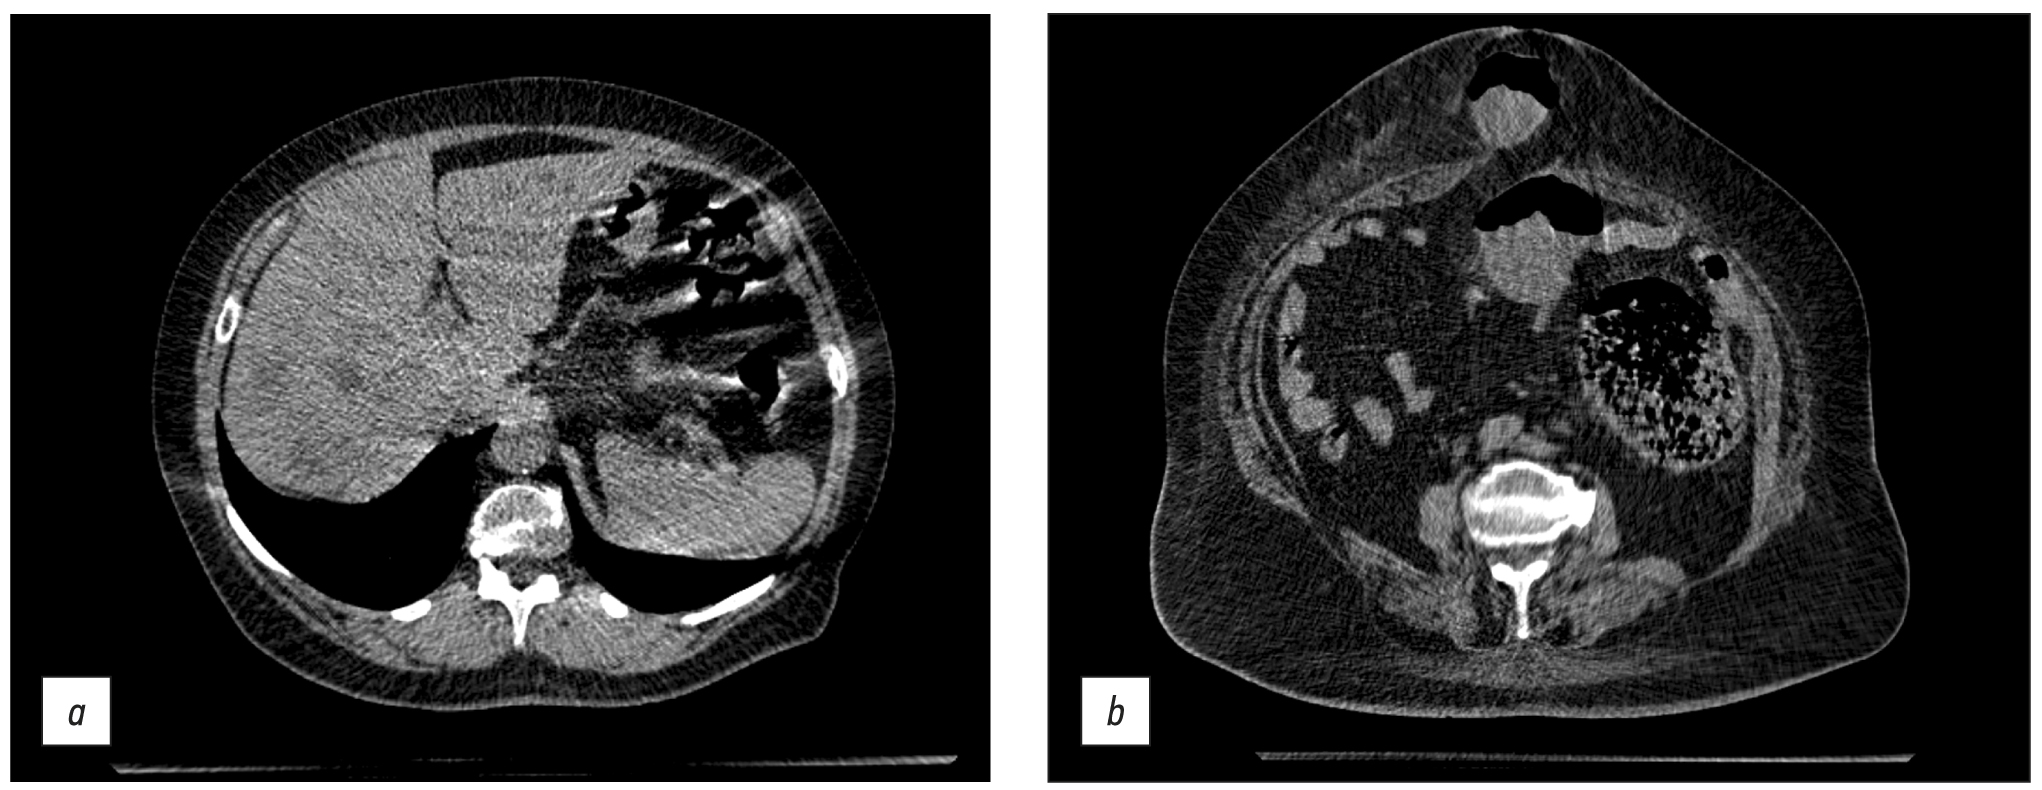

Abdomen CT was used to assess acute abdominal problems, such as suspected intestinal blockage, and detect free liquid or gas (Fig. 9).

Fig. 9. Axial computed tomographic images of the abdomen: (a) CT image of multiple hypodense lesions of both liver lobes, helical artifacts, and gas interface artifacts in the intestinal area and (b) CT image of a strangulated umbilical hernia.

Artifacts were also identified during abdomen CT at the point of contact of various density media, such as intestine gas and surrounding soft tissue (gas-interface artifact) and helical scanning artifacts.

The scanning parameters (Table 1) enable the acquisition of images of sufficient quality for the diagnosis of abdominal and retroperitoneal disorders (liver steatosis, gallstone disease, adrenal hyperplasia and incidentaloma, kidney cysts and urolithiasis, focal liver lesions, and other conditions).